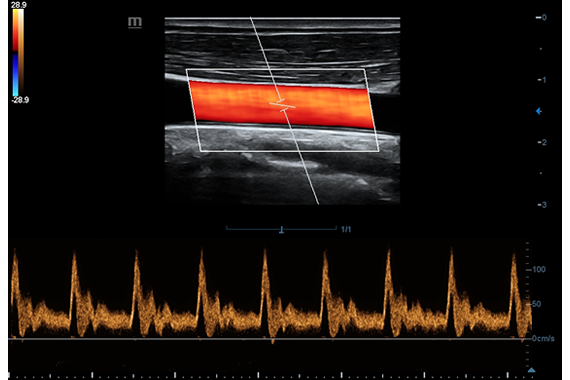

• HR Flow - режим отображения кровотока с высоким временным и пространственным разрешением для точной и однородной визуализации сосудов, в том числе самых мелких.

Цветовой допплер:

Импульсно-волновой допплер:

• HR Flow - режим отображения кровотока с высоким временным и пространственным разрешением для точной и однородной визуализации сосудов, в том числе самых мелких